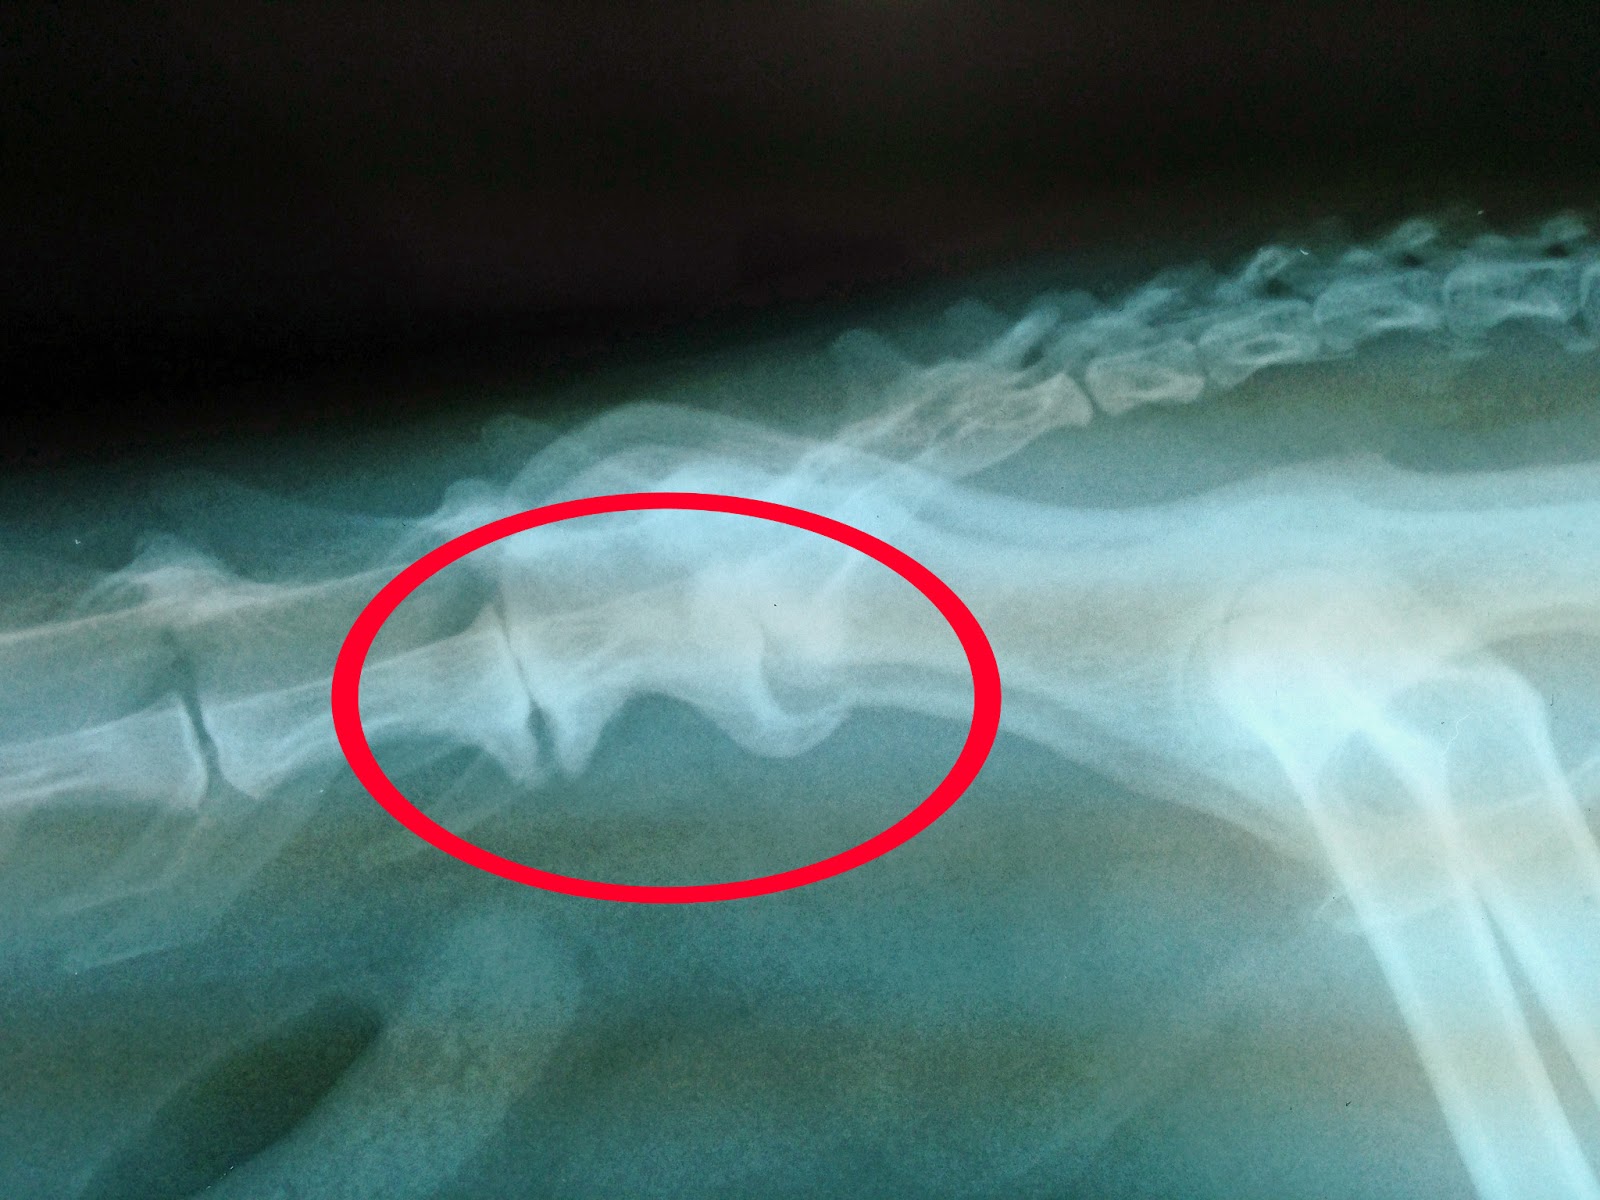

Cat With Arthritis In Spine . It is an especially common health condition in senior cats. yes, cats do get arthritis. first, cats with arthritis don’t limp the way dogs with arthritis often do. Over time there is a. all these studies show that arthritis is actually very common in cats, that it is much more common (and more. according to international cat care (icc), 90% of cats over 12 years of age, had evidence of arthritis. Plus, cats hide any other symptoms they may have so you have to be a pet. 2 in both studies, osteoarthritis was most prevalent in the shoulders, elbows, spine, coxofemoral joints, and tarsi. spinal arthritis is also common in cats, usually affecting the lower back and head of the tail (lumbosacral region). And while the root cause of osteoarthritis in cats isn't. a second study reported that 90% of cats older than 12 years of age had radiographic evidence of osteoarthritis, even though only 4% of these had any mention of arthritis by either owner or veterinarian. In one study, 90% of cats over the age of 12 had. the disease most commonly affects the spine, hip, knee, ankle, and elbow joints in cats. The joints most commonly affected.

Cat With Arthritis In Spine And while the root cause of osteoarthritis in cats isn't. Plus, cats hide any other symptoms they may have so you have to be a pet. the disease most commonly affects the spine, hip, knee, ankle, and elbow joints in cats. first, cats with arthritis don’t limp the way dogs with arthritis often do. all these studies show that arthritis is actually very common in cats, that it is much more common (and more. And while the root cause of osteoarthritis in cats isn't. yes, cats do get arthritis. according to international cat care (icc), 90% of cats over 12 years of age, had evidence of arthritis. spinal arthritis is also common in cats, usually affecting the lower back and head of the tail (lumbosacral region). Over time there is a. The joints most commonly affected. It is an especially common health condition in senior cats. 2 in both studies, osteoarthritis was most prevalent in the shoulders, elbows, spine, coxofemoral joints, and tarsi. In one study, 90% of cats over the age of 12 had. a second study reported that 90% of cats older than 12 years of age had radiographic evidence of osteoarthritis, even though only 4% of these had any mention of arthritis by either owner or veterinarian.

Spinal diseases Cat With Arthritis In Spine 2 in both studies, osteoarthritis was most prevalent in the shoulders, elbows, spine, coxofemoral joints, and tarsi. Over time there is a. It is an especially common health condition in senior cats. the disease most commonly affects the spine, hip, knee, ankle, and elbow joints in cats. In one study, 90% of cats over the age of 12 had.. Cat With Arthritis In Spine.